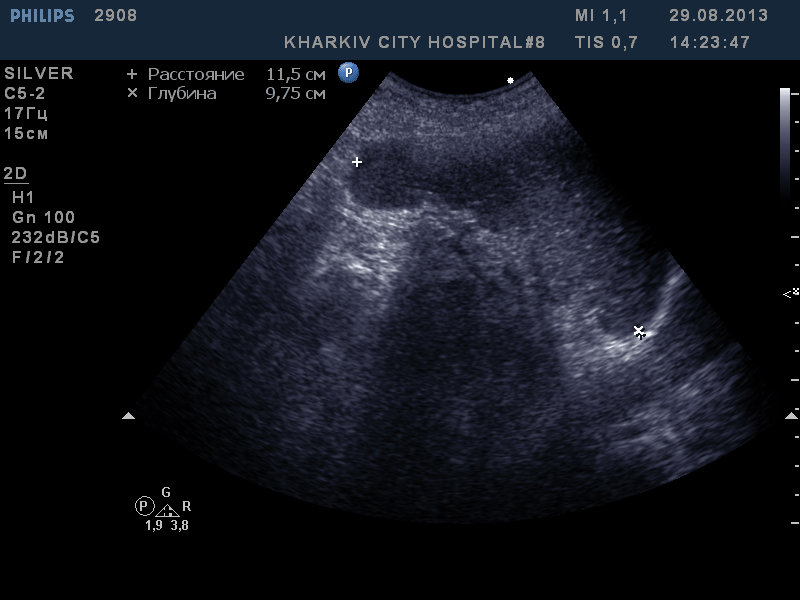

Пожилая пациентка с анемией.

Еще нужно "пройтись" по толстой кишке - особенно по правому изгибу - поискать СППО

Thanks. покручу ее еще, по Вашей рекомендации в проекции толстой кишки

:!: